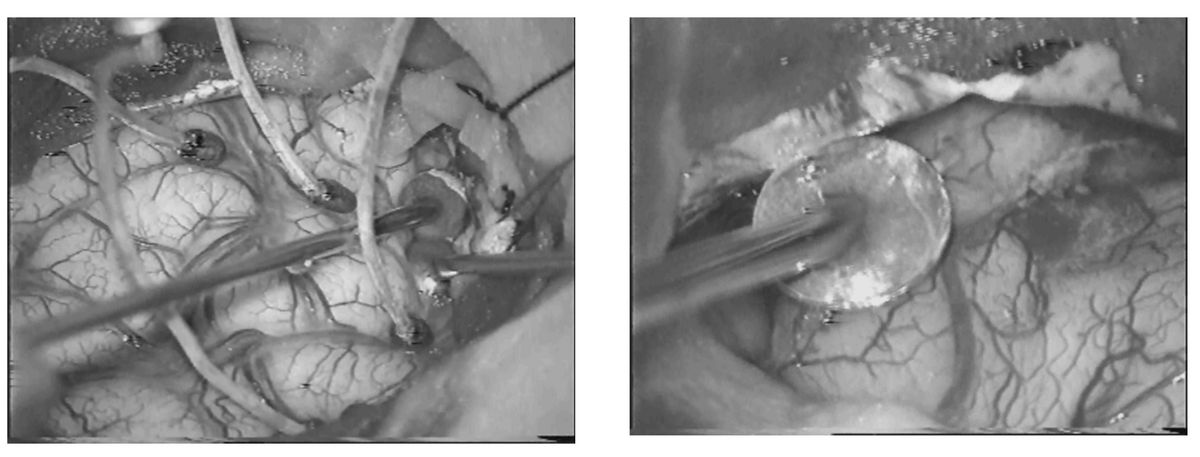

Clinical and experimental perioperative studies are divided into three different phases: before surgical intervention (preoperative studies), during the intervention itself (intraoperative studies), and after a part of the brain has been removed and is available for further investigation (postoperative studies).